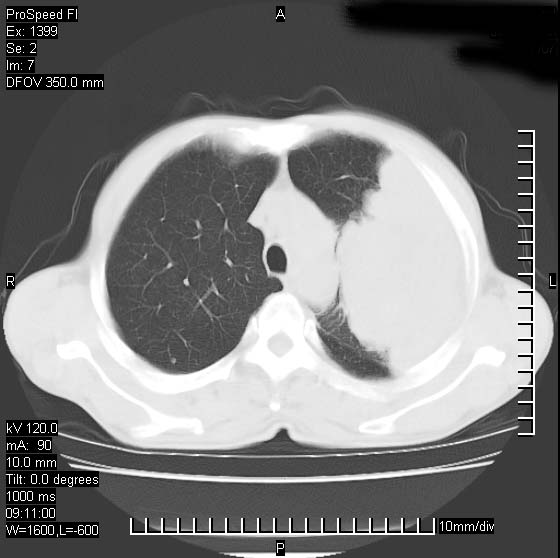

以下是引用卜一在2007-1-19 9:55:00的发言:[br]左肺沿胸膜下巨大肿块影,边缘呈分叶征,纵隔内见肿大淋巴结,右肺内另见一不规则结节影 .考虑:左肺周围性肺癌伴纵隔 右肺内转移.

以下是引用rgsyyf在2007-1-19 11:05:00的发言:[br]左肺上叶见形态不规则巨大软组织肿块影,边缘呈分叶征,纵隔内隆突下见肿大淋巴结,右肺内另见一不规则结节影 .考虑:左肺周围性肺癌伴纵隔即右肺内转移.